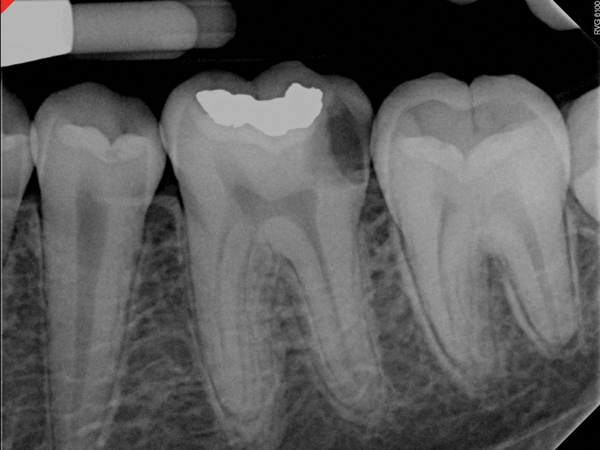

Fig 6. Preoperative radiograph of carious exposure on tooth No. 19. Courtesy of Dr. Mohammed A. Alharbi.

Figure 6

Case 1: Direct Pulp Cap

Figure 6 shows the preoperative radiograph of an apparent carious exposure on tooth No. 19 of a 20-year-old male patient. A diagnosis of reversible pulpitis was made based on the history and clinical exam. After anesthesia and caries removal, the exposure was seen (Figure 7) and covered with BC RRM-Fast Set (Figure 8). After the BC base had fully set, a bonded resin was placed and a postoperative radiograph taken (Figure 9). At the 6-month follow-up visit, the tooth was asymptomatic and tested vital. Radiographically, no signs of pathology were noted (Figure 10).